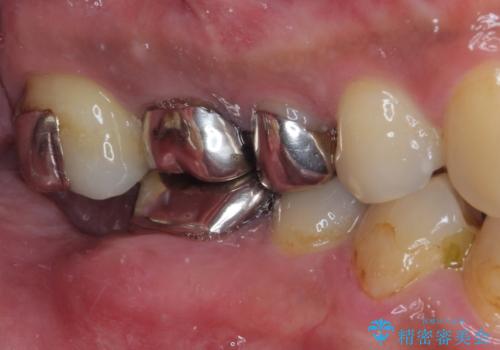

目立つ金属をすべてセラミックに 全顎的メタルフリー治療

- 黄ばんだ前歯や目立つ奥歯の銀歯をきれいにしたいとのことで来院された患者様です。

欠損している歯や、割れてしまって抜歯の必要な歯などがあり、咬合力が強いため欠損部はインプラント補綴を前提に治療を行うこととしました。

小さい修復物の銀歯が装着されている歯はセラミックインレーにて、その他はオールセラミッククラウンにて補綴治療を進めることとしました。